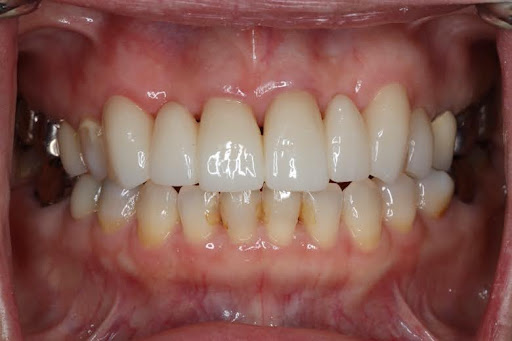

削らず、美しく整える “矯正 × セラミック治療” の治療選択肢

- 無理のない、削らない治療 -

「歯をあまり削りたくない」「でも見た目も整えたい」そんな方のために、矯正とセラミック治療を組み合わせた方法です。先に歯並びを整えることで、必要以上に削らず、自然でキレイな見た目に仕上げることができます。噛み合わせも良くなるため、治療も長持ちしやすいのが特徴です。

このような方に、当院の矯正×セラミック治療のハイブリッド治療は特におすすめです。